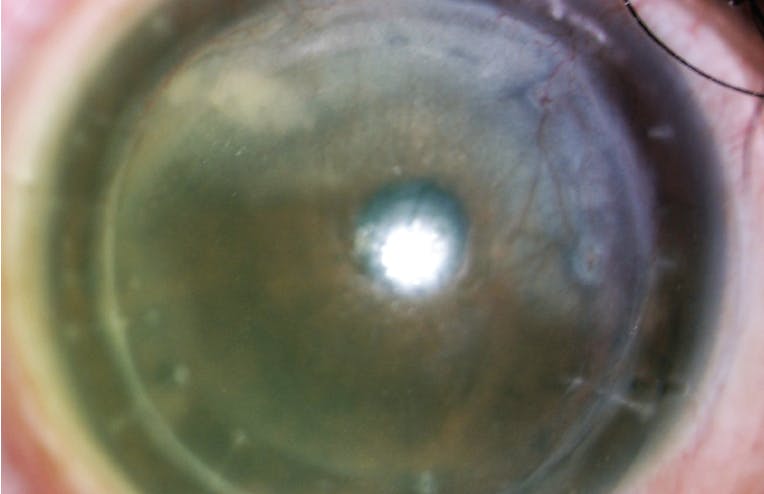

Next, have the patient remove his or her lenses so that anterior segment OCT imaging and wavefront analysis can be performed and keratometry measurements taken. Your goal is to collect enough quantifiable information to analyze and understand the patient’s eye and adnexa. This is also a good time to inspect the eye for signs of neovascularization (Figure 2), especially if the patient has a history of radial keratotomy or penetrating keratoplasty (Figure 3). Look for subtle corneal infiltrates, check the post-wear refraction, assess tear quality and tear breakup time, and evaluate staining of the cornea, the conjunctiva, and the lid margins. Be alert for giant papillary conjunctivitis. Confocal microscopy can help you to scan for polymegethism, edema, and endothelial blebs.